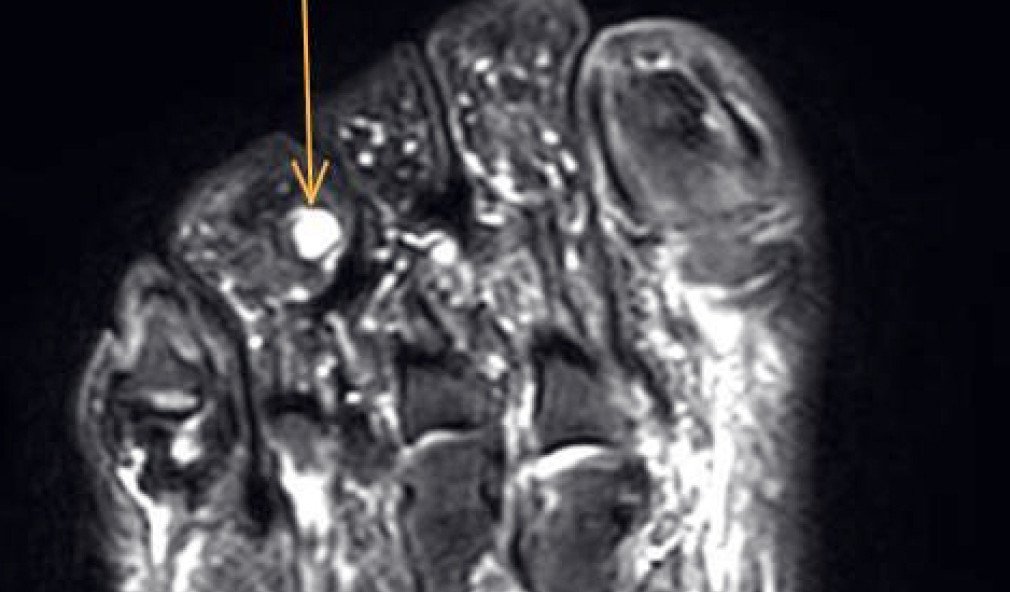

MRI-Bild Fuss mit belastungsinduziertem Logensyndrom

Belastungsinduziertes Logensyndrom des Grosszehen-Spreizer-Muskels

Ein Patient suchte uns wegen starker Schmerzen an der linken Fusssohle beim Joggen auf. Ursache war ein Logensyndrom, auch Kompartmentsyndrom genannt, des Grosszehenspreizer-Muskels. Erfahren Sie im  Fallbeispiel, wie wir zur Diagnose kamen und wie wir dem Patienten mit einer Operation helfen konnten.